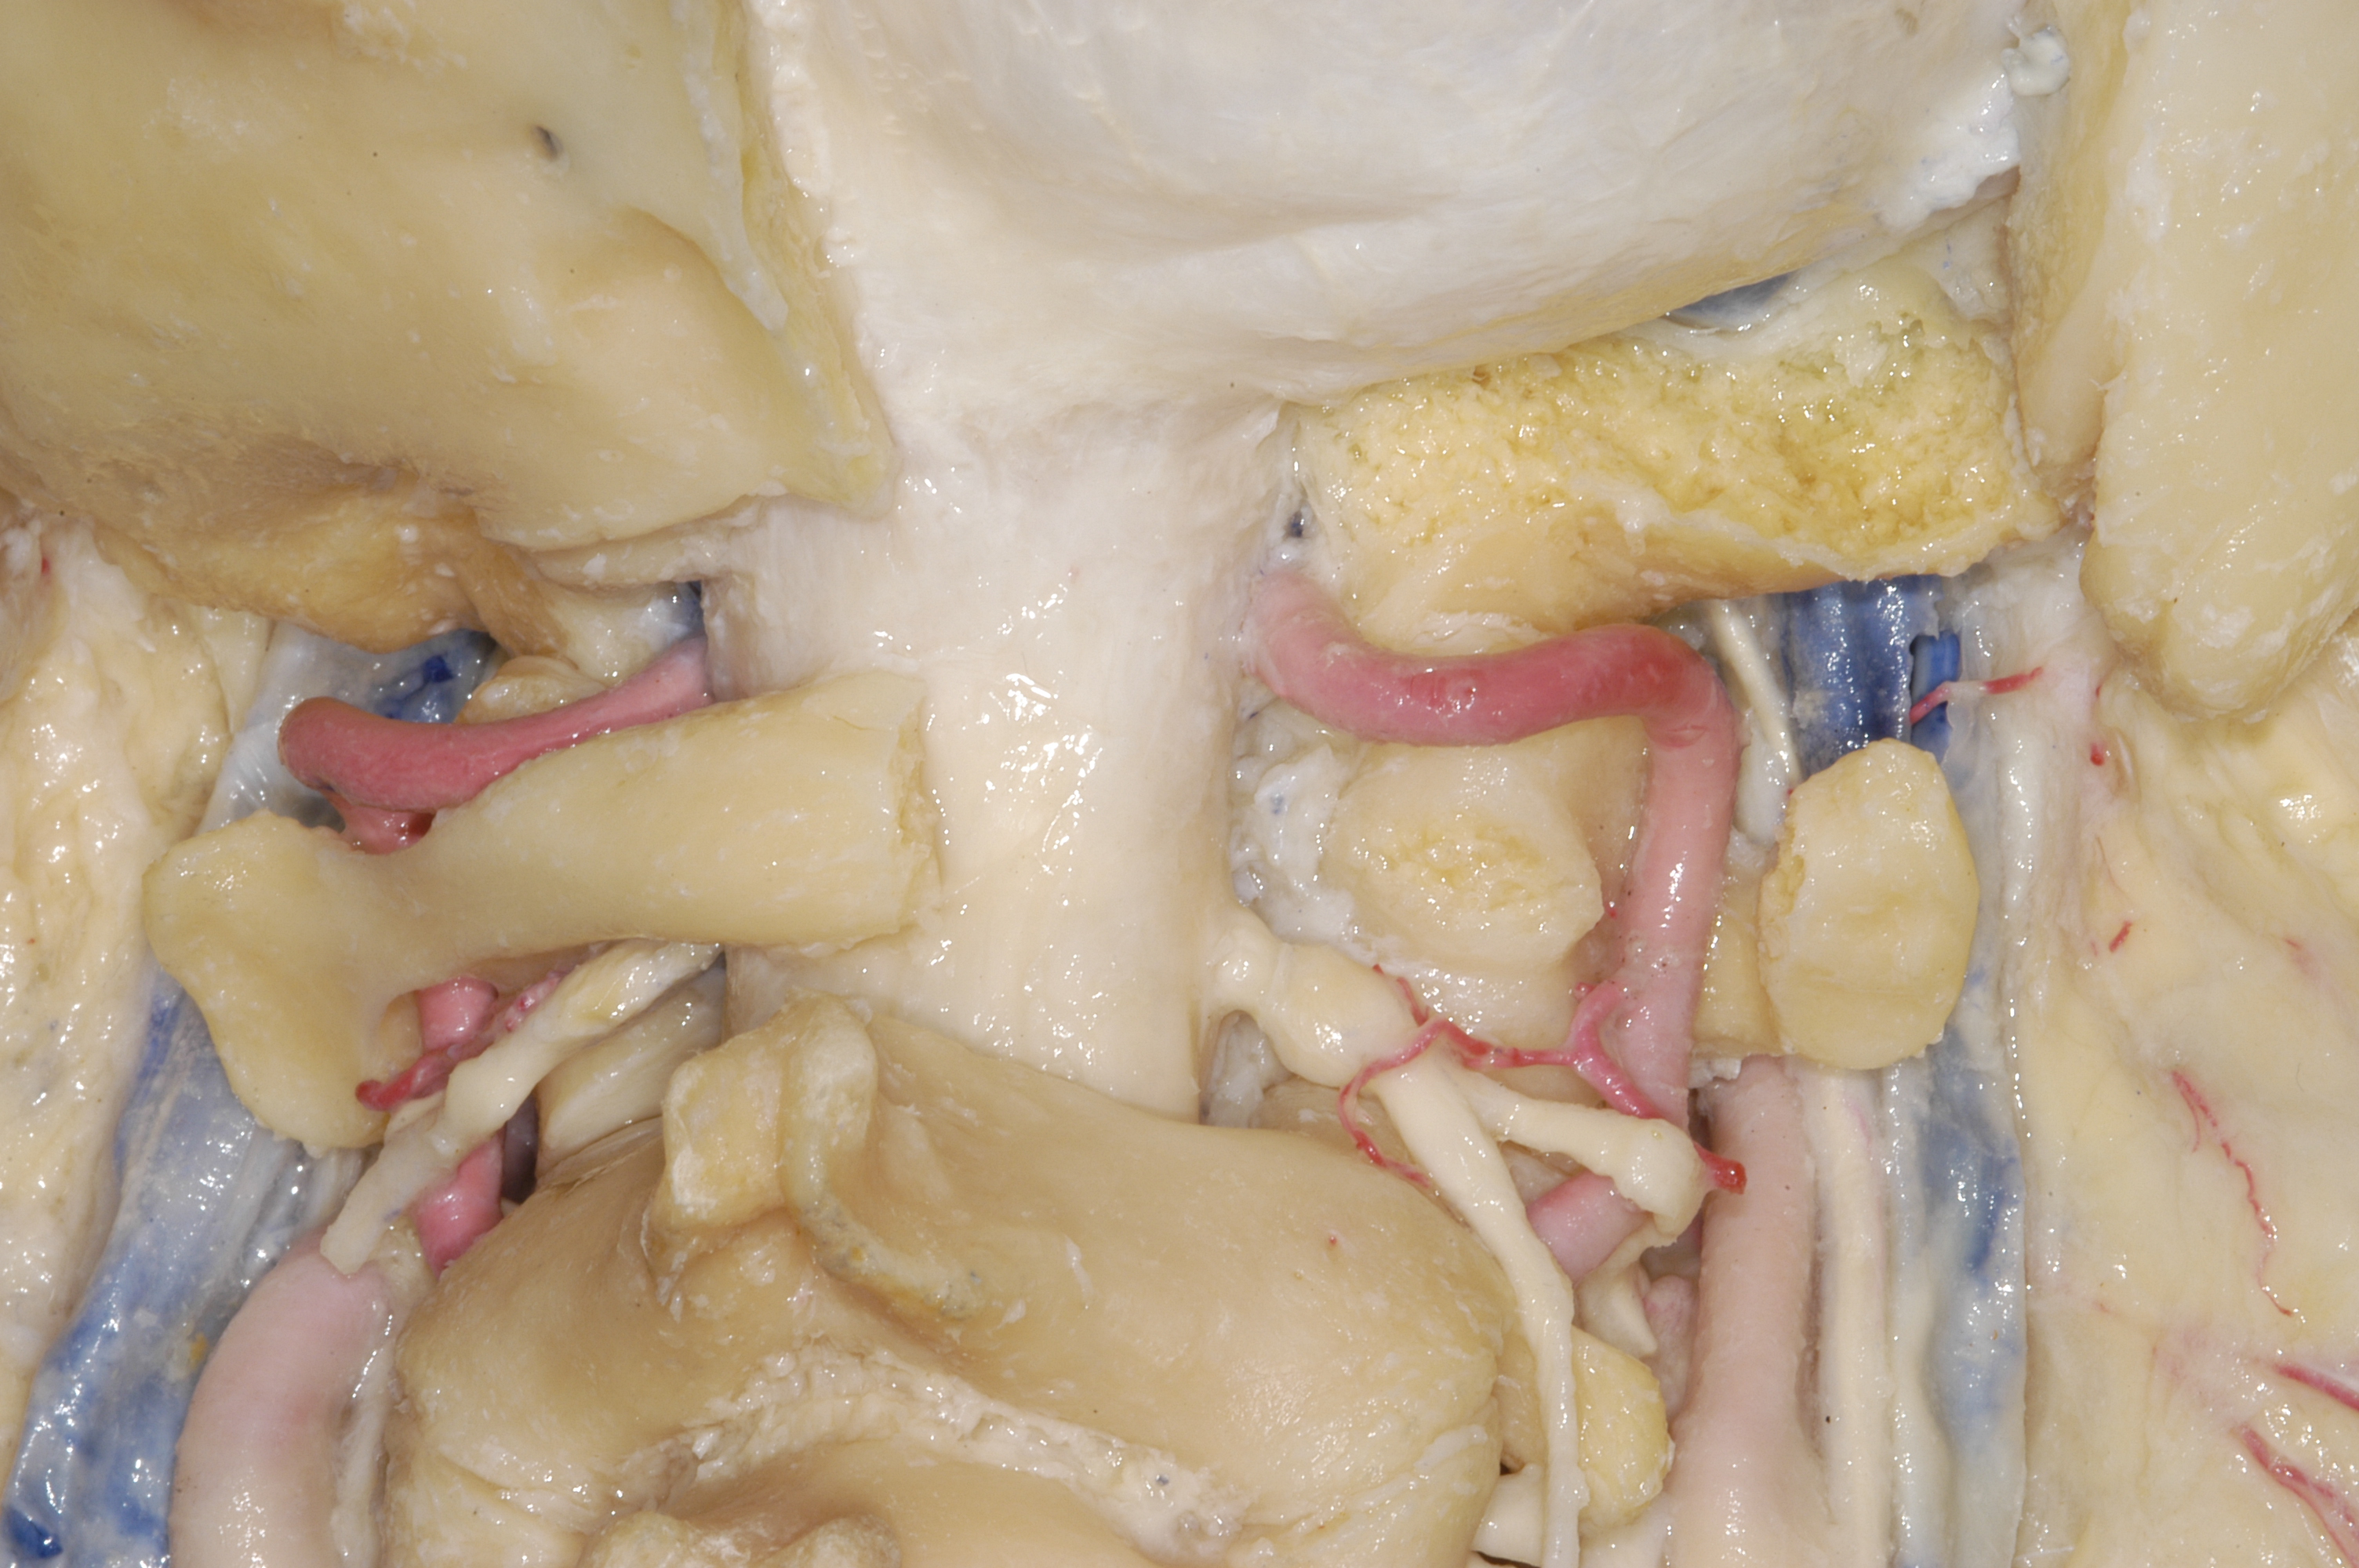

舌下神经管骨性结构

远外侧经髁上开颅逐步过程

有时候会用椎动脉移位,对舌下神经管和颈静脉孔区暴露更好

因为颈静脉孔区毗邻舌下神经管区,所以远外侧髁旁入路和髁上入路都是用耳后C型切口。颈静脉孔区注重暴露颈静脉球部,舌下神经管区注重暴露枕髁。